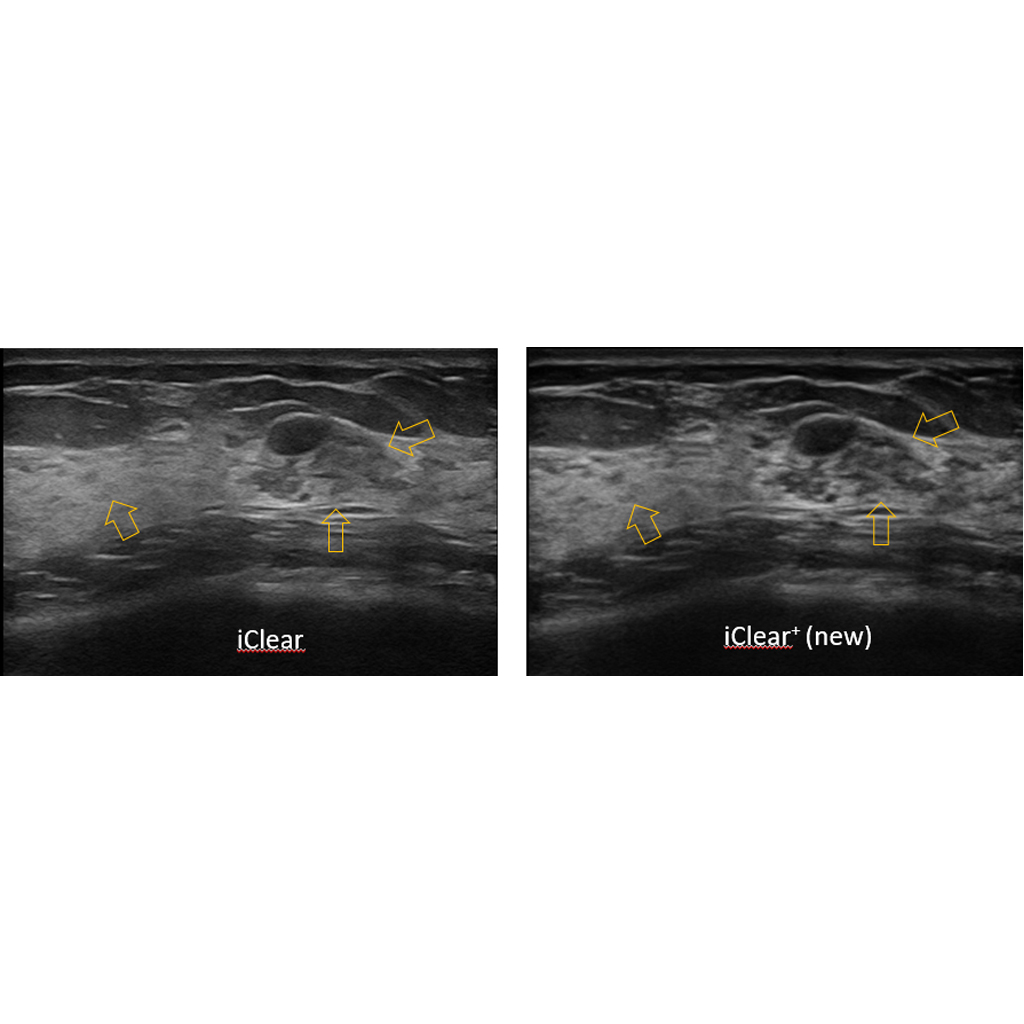

iClear + е последна генерация разширена версия на iClear с допълнително подобрение на качество на изображението, изчистване на шума, осигуряване на по-добър контраст и разделителна способност, и по-лесно идентифициране на лезии